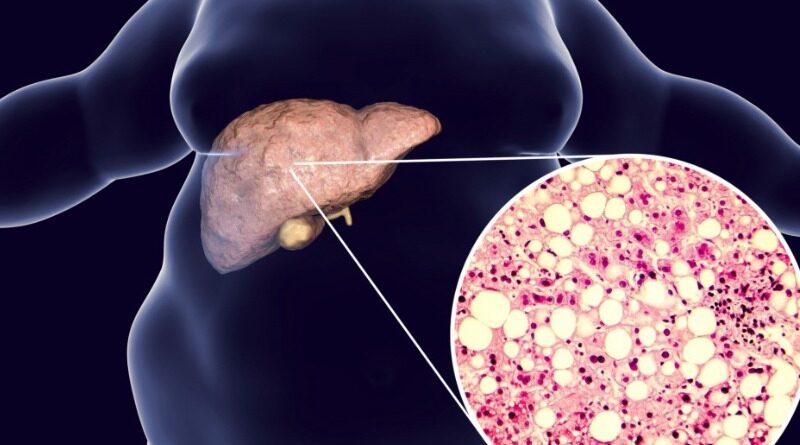

Recomienda IMSS Veracruz Norte alimentación saludable para prevenir hígado graso

Con el objetivo de prevenir complicaciones en la salud y mantener una saludable función hepática, el Instituto Mexicano del Seguro Social (IMSS) en Veracruz Norte recomienda adoptar una alimentación saludable que evite desarrollar hígado graso.

El consumo excesivo de grasas saturadas y azúcares puede favorecer a la acumulación de grasa en el hígado, provocar resistencia a la insulina y aumentar el riesgo de enfermedades metabólicas, tales como: diabetes, obesidad y enfermedades cardiovasculares. El hígado graso no tratado puede evolucionar a hepatitis, cirrosis hepática y cáncer.